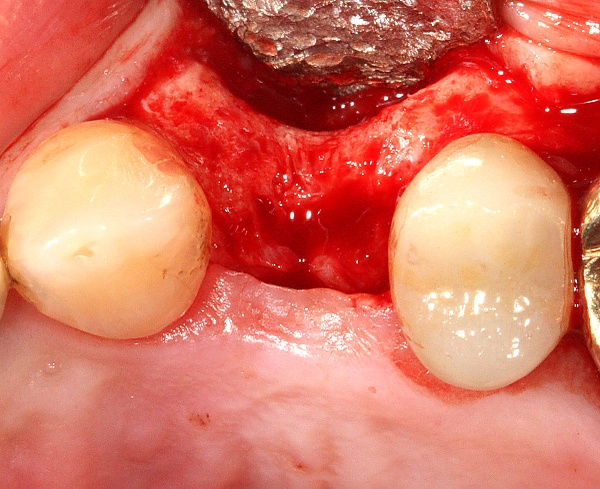

Разборный имплантат состоит из непосредственно имплантата и надстройки (супраструктуры), именуемой абатментом. Такой имплантат может быть установлен по одно- и двухэтапному протоколу. Двухэтапный протокол подразумевает полное погружение имплантата и накрывание его слизистой оболочкой, в результате чего исключается любой контакт имплантата с полостью рта — эта процедура называется первым этапом дентальной имплантации. Второй этап заключается в установке какой-либо надстройки (супраструктуры) — это может быть как формирователь десны, так и абатмент с временной коронкой или другим видом протезной конструкции. После какого промежутка времени будет выполнен второй этап обычно решает имплантолог, опираясь на данные о качестве костной ткани, возраст и общее состояние пациента, а также свой клинический опыт. Классические сроки составляют 4—6 месяцев, однако последнее время существует тенденция к сокращению сроков ожидания до 2,5—3 месяцев. Это связано с лучшим пониманием процесса остеоинтеграции, а также оптимизацией макродизайна и микрохарактеристик поверхности имплантатов.

Особое значение имеет уровень гигиены полости рта. Имплантация не может быть выполнена без санации полости рта (все зубы должны быть вылечены), поскольку любой очаг инфекции в организме может свести на нет работу имплантолога из-за высокой вероятности последующего отторжения вживлённого имплантата.